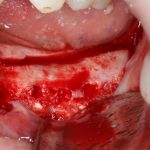

Откроем область операции и посмотрим, что там:

Вроде как, всё неплохо. Наверное, можно поставить имплантаты?

ну, или как-то так:

При этом, я хотел бы обратить ваше внимание на один важный момент. То, с чем вы сейчас работаете — не кость, в привычном нам гистолого-физиологическом понимании. Это костная мозоль вперемежку с графтом. Её свойства довольно сильно отличаются от того, что мы привыкли называть костной тканью. Поэтому при установке имплантатов соблюдайте максимальную осторожность и щадящий режим. Никаких диких торков, усилий, больших переходов между размерами фрез допускать нельзя. Будьте аккуратны.